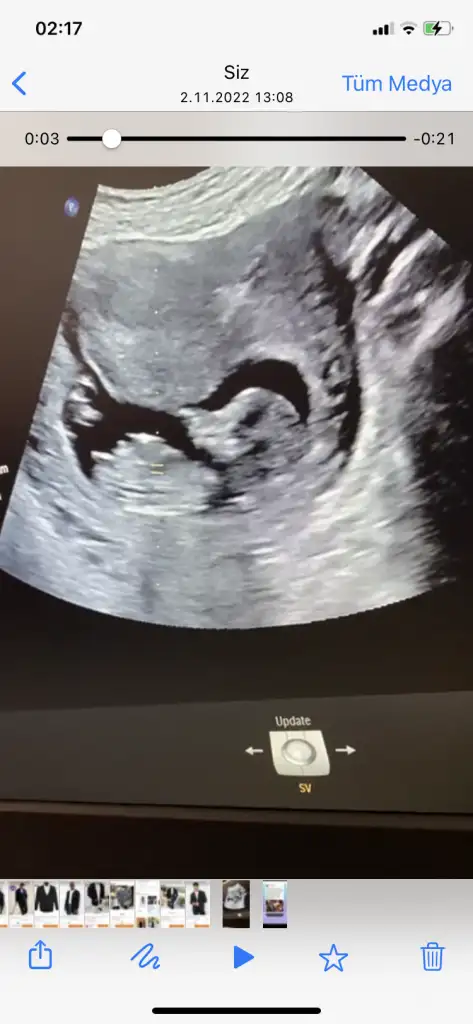

Saglikli olsun bebisim hayirlsi 🤲Bu da 8 haftalik Teyzesi. Bana erkek gibi geliyor